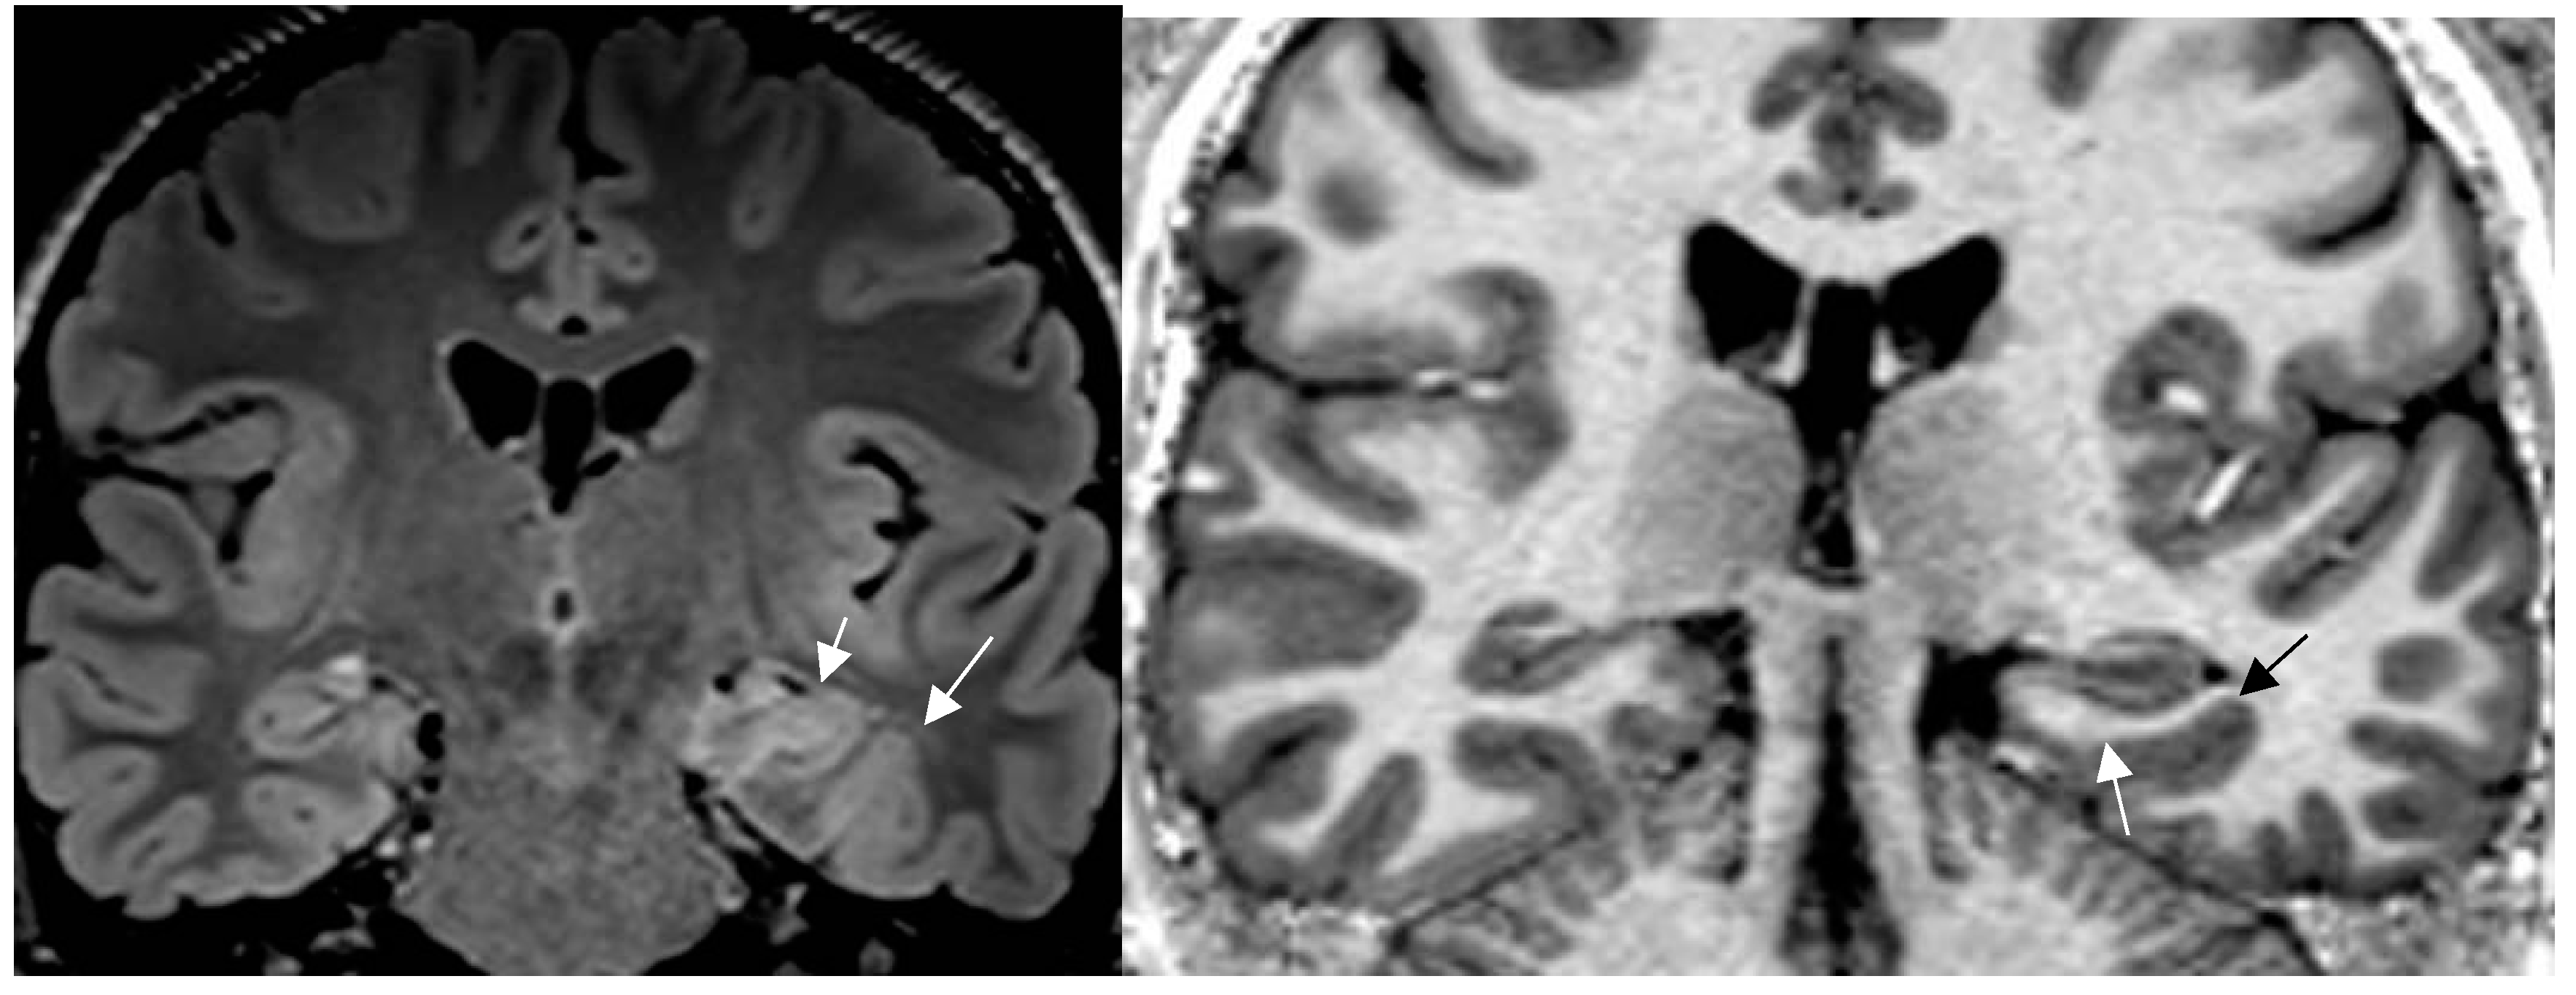

4.1. Pathologies Likely to Be Missed on Brain MRI in Patients with Epilepsy

4.2. A standardized Epilepsy Specific Protocol Provides Superior Diagnostic Yield

4.3. Expert Readers Take Advantage of the Added Value of an Epilepsy Specific Protocol

4.4. Increased MRI Field Strength and Receive Coils Improve Lesion Recognition by Enhanced Signal and Spatial Resolution

4.5. New MR Sequences Display Tissue Properties for Improved Visualization of Lesions

4.6. Postprocessing by Morphometric Analysis Improves Focal Lesion Detection Beyond Visual Analysis

4.7. Postprocessing by Quantitative Analysis of Signal Intensity, Volumetry Enhances Temporal Lesion Identification

4.8. Postprocessing by 3D Surface Rendering Technique to Improve Comprehension of Superficially Located Lesions

4.9. MR Fingerprinting Exploits Tissue Properties to Reflect “Activity“ of a Lesion

4.10. MR Perfusion Exploits Blood Flow to Identify Interictal Laterality of a Focus

4.11. Contrast Administration Is of Limited Gain with Respect to Lesion Detection But May Contribute to Characterization of an Abnormality

4.12. New Entities: Knowledge Shapes Perception